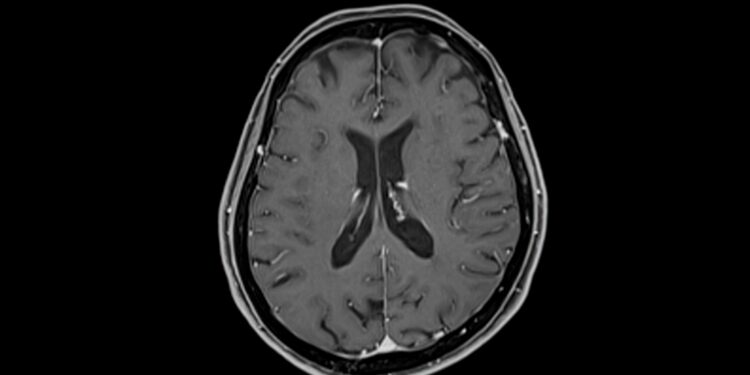

Kai tik įtariama ši būklė, svarbu nedelsti – diagnozė nustatoma skubių neurologinių tyrimų ir paciento savijautos, ligos, kelionių istorijos analizės pagrindu. Papildomai gali būti atliekami kraujo tyrimai (pvz., nustatyti uždegiminius rodiklius ar elektrolitų disbalansą), taip pat galvos smegenų tyrimai magnetinio rezonanso arba kompiuterinės tomografijos pagalba.